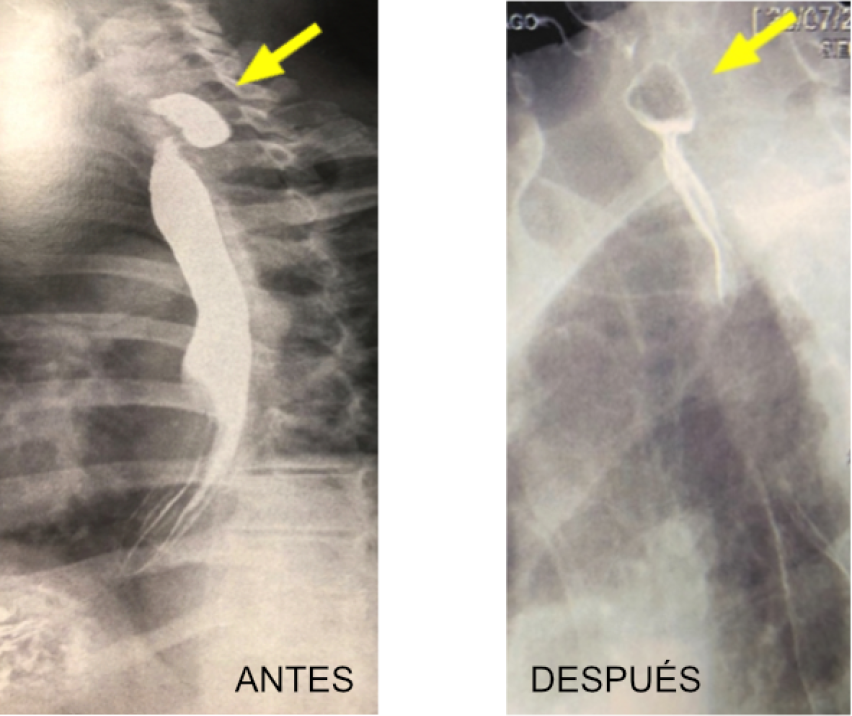

Divertículo de Zenker

Los divertículos son trastornos por una disfunción del músculo cricofaríngeo, apareciendo un falso divertículo en la unión faringo-esofágica, el cual pierde su capacidad de relajación durante la deglución. Debido al aumento de la presión hipogaríngea se produce una herniación de la mucosa y submucosa, produciéndose una fusión de la adventicia y formándose un tabique que separa la luz esofágica de la luz diverticular.

Anteriormente el tratamiento de esta patología era únicamente quirúrgico, pero en la actualidad debido al avance de las técnicas se puede tratar mediante endoscopia digestiva. Así, se disminuye el riesgo que tiene la cirugía y el paciente permanece hospitalizado tan sólo 8 horas, siendo dado de alta con una dieta especial durante unos días. Los síntomas desaparecen desde el primer momento.